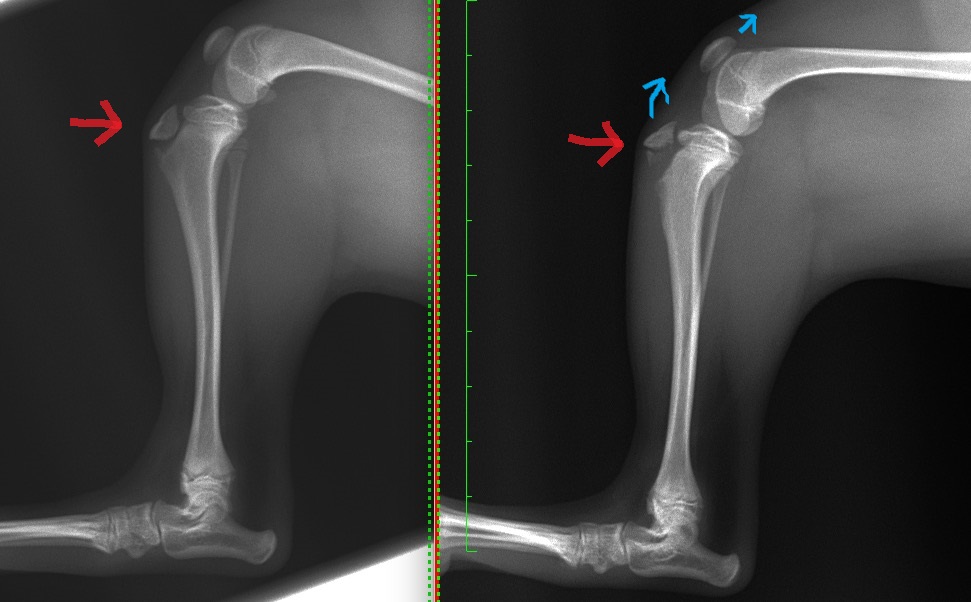

脛骨粗面剥離骨折の幼犬の1例(整形外科、後肢、膝)

視診、触診(整形外科学的検査)、歩様検査を実施し、左後肢の跛行と左膝関節の腫脹・疼痛が見られたため、X線検査を行いました。

X線検査の結果、外傷性の脛骨粗面剥離骨折が強く疑われました。

脛骨粗面(赤矢印)とは、膝の膝蓋靭帯が脛骨(すねの骨)の付着している部位であり、大腿四頭筋群や膝蓋骨とも連絡し、強い力がかかります。

成長期ではまだ完全に骨化していないのでX線では周囲が黒く抜けて見えていますが、写真右側の患肢は骨折があるため大腿四頭筋群や膝蓋靭帯の強い力で引っ張られ上方に変位(水色矢印)してしまっているのが分かるかと思います。

これにより、膝関節周囲の腫れや疼痛が引き起こされていました。